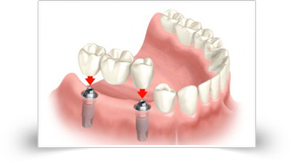

Multiple Teeth Missing

If more than one tooth is missing in different parts of the mouth, multiple single tooth implant are efficient substitute restorations. If multiple teeth are missing in the same region, multiple missing teeth can be replaced with fewer implants because dental implants are tougher than the natural tooth roots. This solution comprises implants, fixed bridges done

If more than one tooth is missing in different parts of the mouth, multiple single tooth implant are efficient substitute restorations. If multiple teeth are missing in the same region, multiple missing teeth can be replaced with fewer implants because dental implants are tougher than the natural tooth roots. This solution comprises implants, fixed bridges done